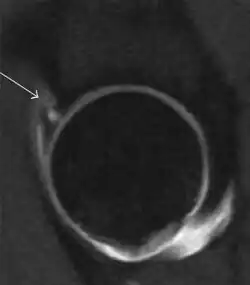

Most of the angles and measurements described in the plain radiograph section can be accurately reproduced on MRI. In addition, the superiority of MRI resolution with intra-articular contrast allows detection of labral and chondral abnormalities that may influence the choice of medical, percutaneous, or surgical management (Figure 9).[1]

Figure 9:

Sagittal CT-arthrography showing posteroinferior chondral injury.[1] -

Coronal CT-arthrography (d) showing ligamentum teres tear.[1]